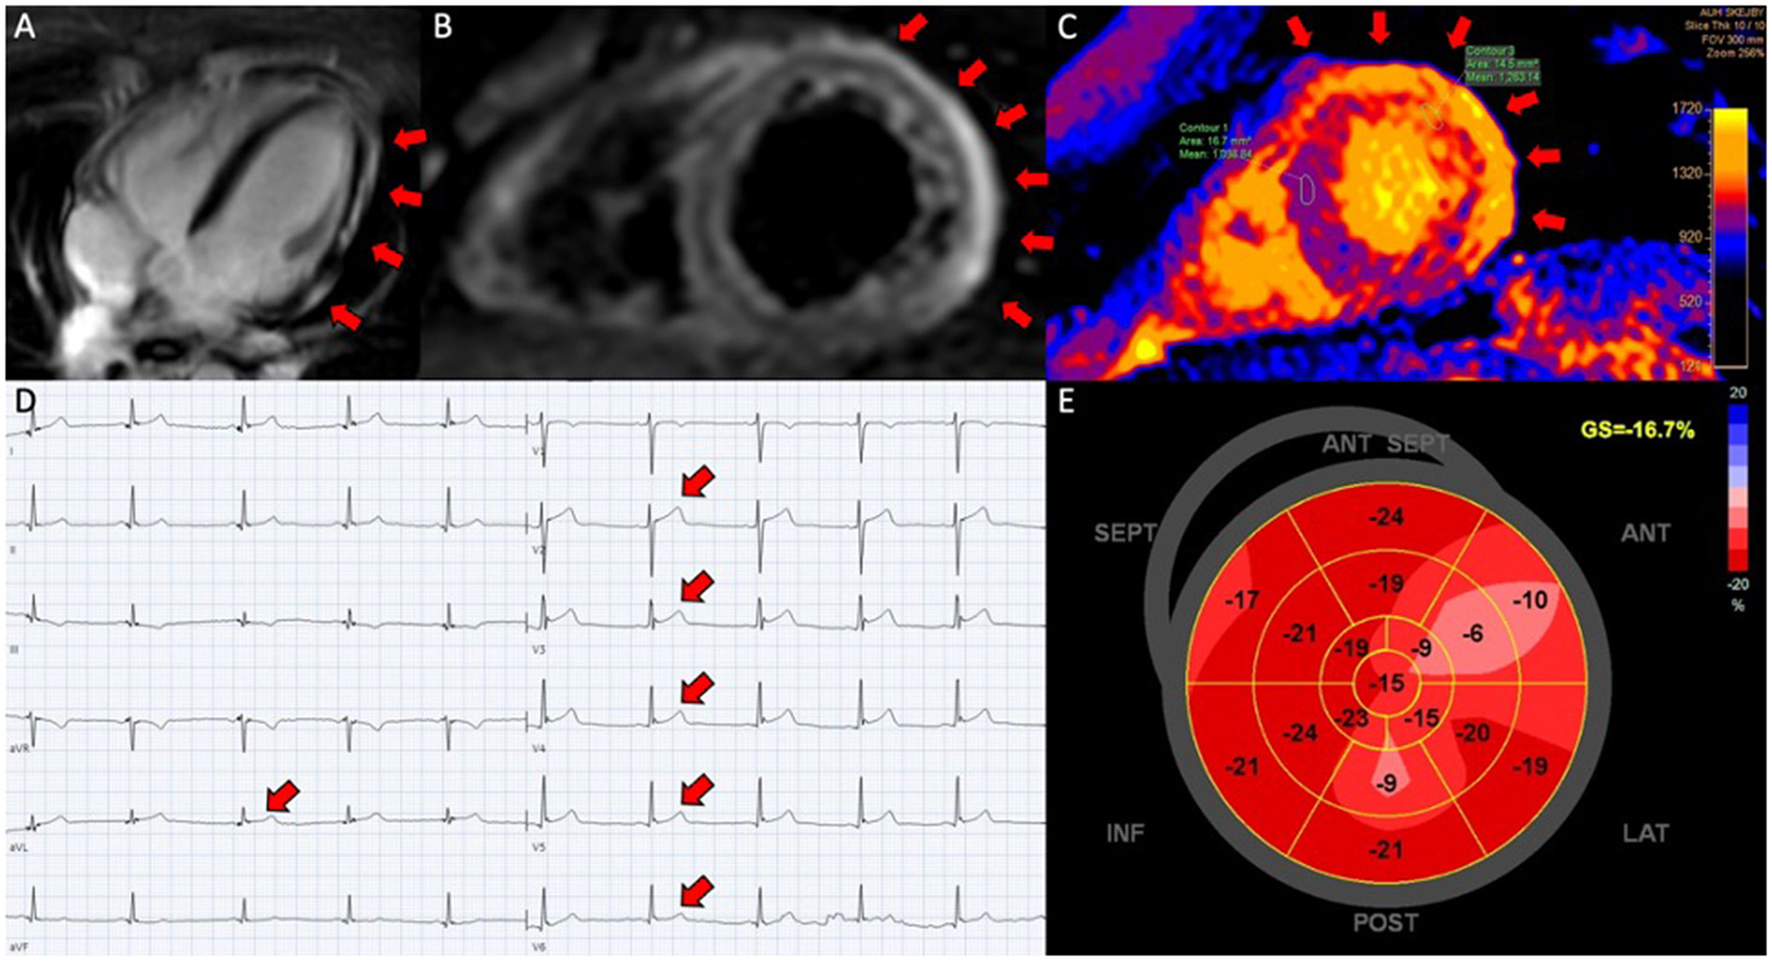

Figure 1

Perimyocarditis in a patient (case 3). (A) Late gadolinium enhancement in the epicardium at the lateral segments in 4-chamber view; (B) CMR, short axis T2-weigthed image showing hyper-intensive signal in the epicardium along the lateral segments indicative of oedema; (C) T1-map in short axis showing increased T1 values up to 1,191 ms at the lateral segments reflecting myocardial injury; (D) electrocardiogram showing ST-elevations in lead V2-V6 and aVL; (E) 17-segment plot of global longitudinal strain on echocardiography with decreased values antero-laterally.